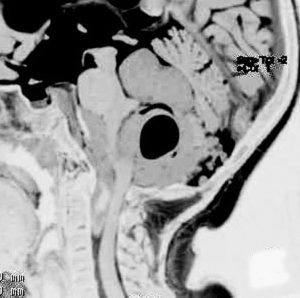

第4脳室上衣腫(良性と言える思春期例:EPN-PFB)

青年に発生したものです。かなり分化度の高い延髄背側 ovex 発生の上衣腫です。境界が明瞭なのですが,実際に側方(延髄小脳脚槽)で椎骨動脈や後下小脳動脈,下位脳神経に癒着しているので剥離は必ずしも容易ではありません。この例では幸い全摘出できました。